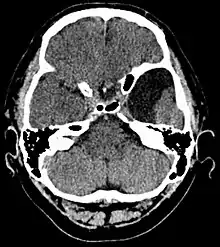

Diagnosis is principally by MRI. Frequently, arachnoid cysts are incidental findings on MRI scans performed for other clinical reasons. In practice, diagnosis of symptomatic arachnoid cysts requires symptoms to be present, and many with the disorder never develop symptoms.